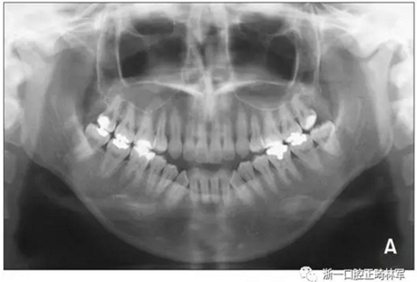

全景片顯示四顆智齒都存在,上頜切牙有牙根吸收,并且在雙側(cè)髁突都有相當(dāng)大的吸收(Figures 1B and 5A)。頭測分析顯示:ANB angle, 4.5°; FMA, 46.7°; U1-SN, 95.8°; L1-MP, 83.7°(Table 1, Figure 5B)。

基于上述檢查結(jié)果,患者被診斷為雙側(cè)髁突形態(tài)改變引起的開合畸形。